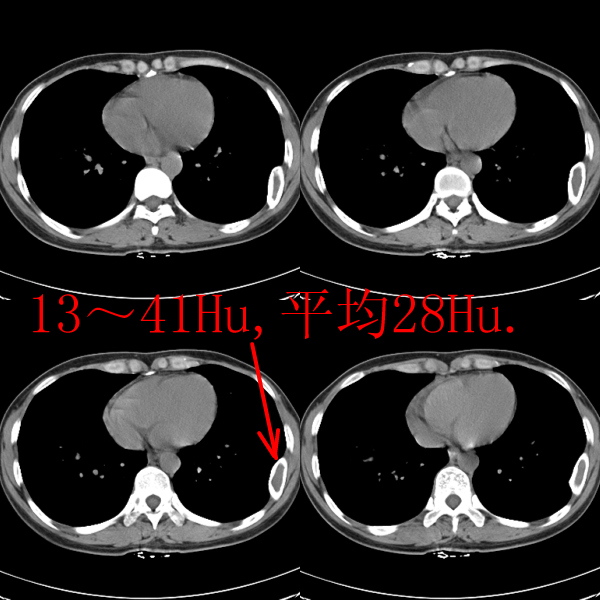

标题: CT19623:F40y,肋骨改变。

40岁女性,双侧胸部疼痛,以左侧为明显1+年。余无明显异常。

左侧肋骨单发膨胀性病变,皮质连续,病史较长,首先考虑良性病变:骨纤可能性大。